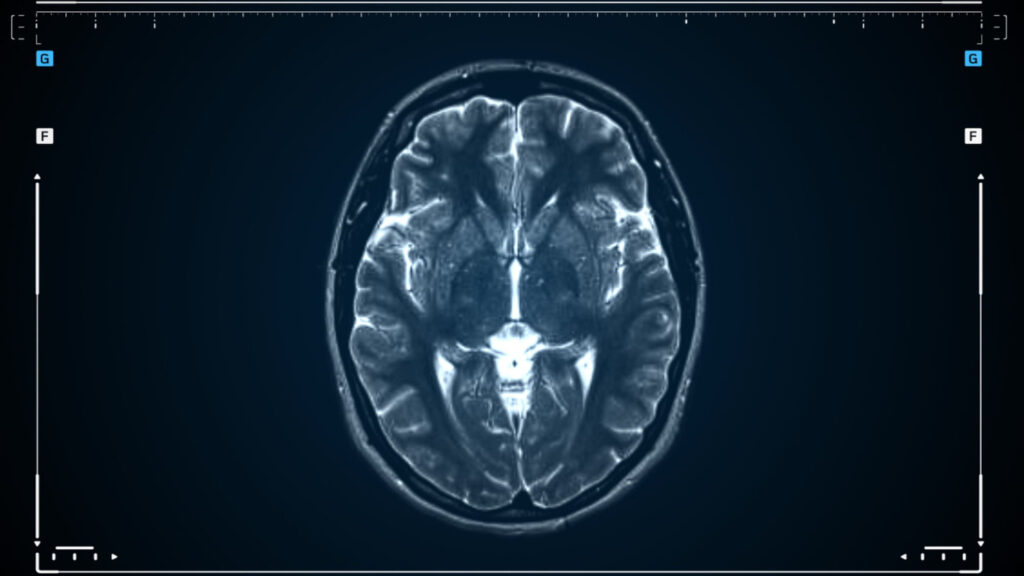

Advanced imaging is key in checking brain tumors. We use MRI and CT scans to see where the tumor is, how big it is, and what it’s like. These tools help us plan the surgery by showing how the tumor affects the brain around it.

Advanced imaging is key in finding brain tumors. MRI and CT scans give us detailed pictures. This helps our surgeons plan the best surgery.

Our team uses MRI and CT scans to check the tumor’s location and size. We also look at the patient’s health and the surgery risks.